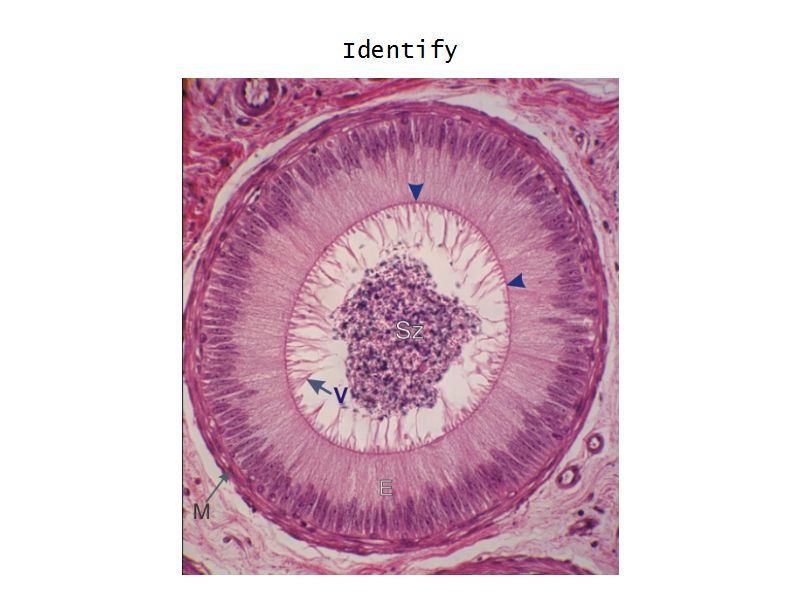

Epididymus

- Long convoluted duct

- With fibrous covering

- Inside visceral layer of tunica vaginalis testis

Epididymus

- Simple ciliated columnar epithelium

- Tall ciliated cells

- Elongated nuclei away from BM

- Low absorptive cells

- Spherical nuclei close to BM

- Surrounded circular smooth muscle